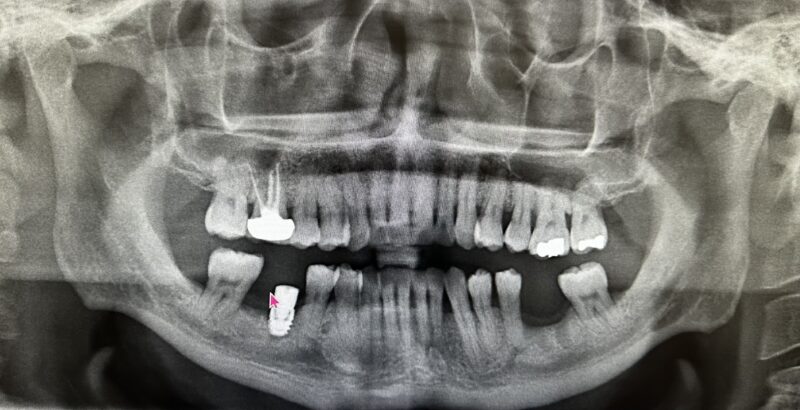

The case I am sharing has been quite challenging for me restoratively. Patient was referred out for implant placement #31. It is a Nobel implant WP. First time I restored it, within a week of insert abutment fractured. Fortunately, retrieving the abutment screw was not that difficult. When I inserted the first time I did know something is…

This one is a bit tough. I say that because it looks like it was a little difficult on the surgical aspect with minimal bone height. It always seems to work out this way–in the cases where you wish to have no problems, you often encounter them.

It’s okay though. Let’s try to get to the bottom of this.

First: I understand you cemented the crown…